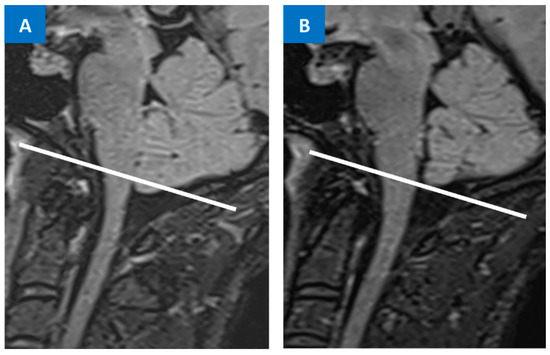

- Houk, J.L.; Amrhein, T.J.; Gray, L.; Malinzak, M.D.; Kranz, P.G. Differentiation of Chiari Malformation Type 1 and Spontaneous Intracranial Hypotension Using Objective Measurements of Midbrain Sagging. J. Neurosurg. 2021, 136, 1796–1803. [Google Scholar] [CrossRef]